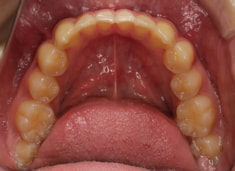

小児期ケース:反対咬合+上顎両側3番埋伏歯

(受け口+3番目の永久歯が左右両方とも埋まってしまい、はえてこない)

治療法:上顎急速拡大装置+クリアスナップ+フェイスマスク+上顎3番は開窓牽引CT写真にて位置確認